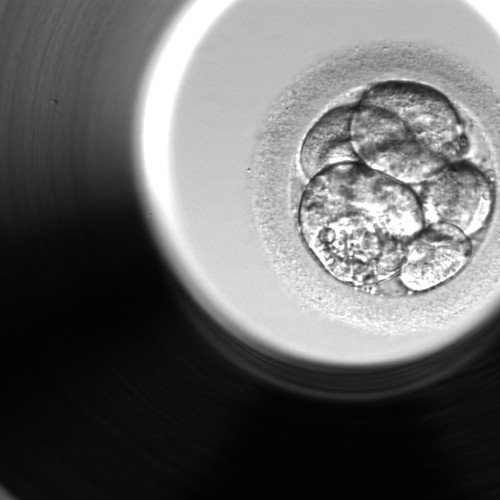

wie schätzen Sie diesen Kryo ein? Er ist ein 8-Zeller Note 2 am Tag 5.

Macht dieser Embryo Sinn für ein Transer?

der Entwicklungsstand des Embryos entspricht dem Stadium, das man bei einer zeitgerechten Entwicklung an Tag 3 erwartet. Wenn ein Embryo an Tag 5 im 8-Zell-Stadium ist, muss man davon ausgehen, dass die Weiterentwicklung stehen geblieben oder sehr stark verzögert ist, leider nur sehr geringe Chancen für eine erfolgreiche Einnistung.